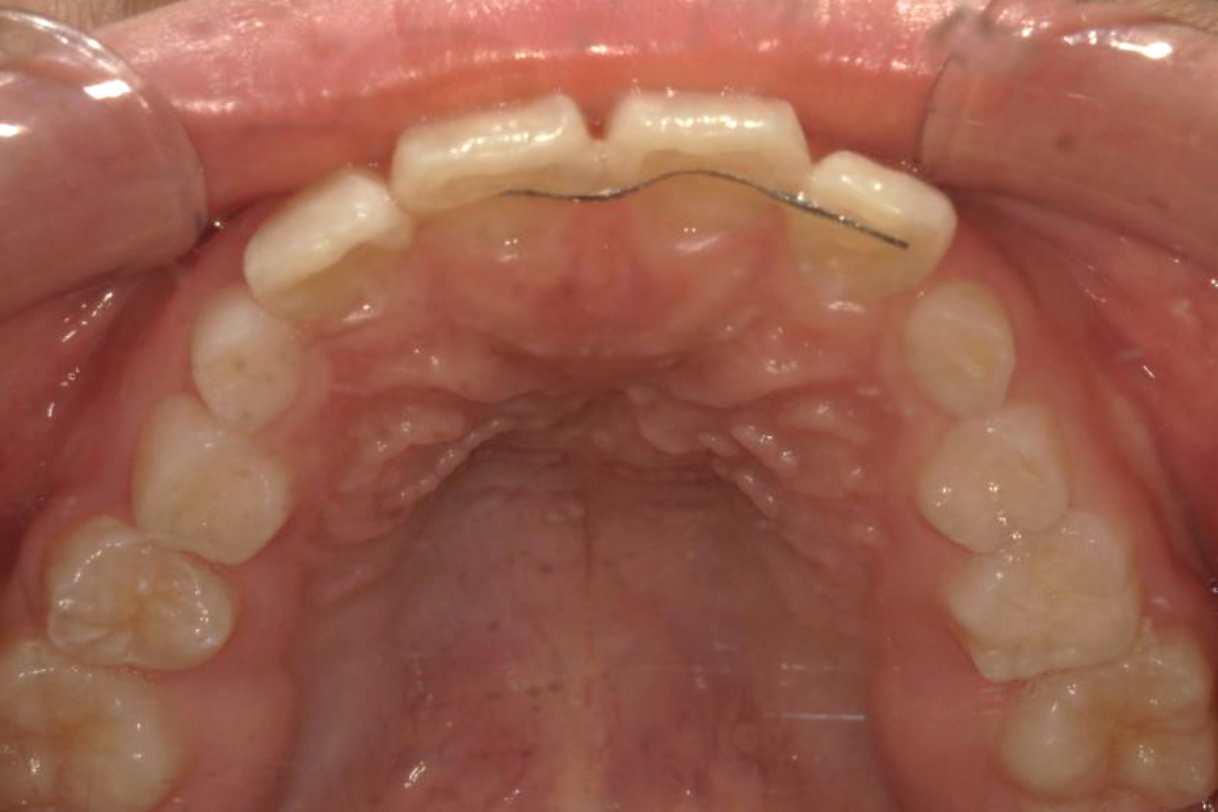

初診時年齢:7歳

治療:前歯部矯正

治療法:上顎前歯部表側の装置

治療期間:2ヶ月

費用:110,000円(税込)

リスク・副作用:装置装着による違和感、歯の移動時の痛み